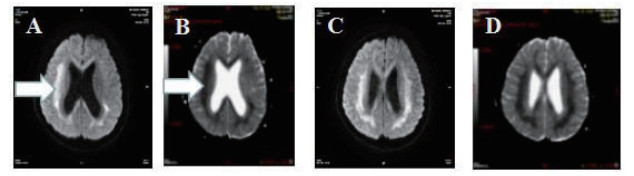

2 结果 2.1 基本资料及头颅核磁特征本观察研究最终纳入患者51例,中毒患者的头颅核磁特征表现为:在MRI的常规序列(T1\T2\FLAIR)病灶显示不明显,但在DWI表现为高信号,ADC值下降呈低信号。病变部位主要是胼胝体的压部(所有阳性病例胼胝体压部均受损),病变也可以形成以胼胝体为中心的广泛白质病变,皮质不受损害。见图 1,2。

| 图 1 A.T1序列/B.T2序列/C.FLAIR序列均无异常;D.DWI系列上为高信号(箭头所示) |

| 图 2 A\C弥散像呈高信号,B\D ADC图呈低信号(箭头所示) |